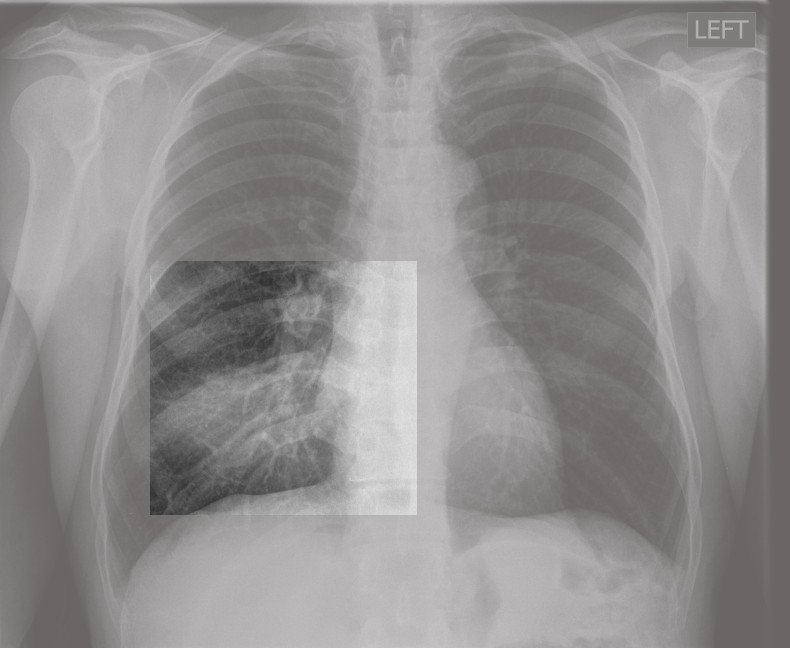

Polmonite

Malattia che si caratterizza per l'infiammazione del tessuto polmonare, ovvero degli spazi interalveolari (interstizio) e dei bronchioli. Può avere diverse cause, la principale è quella infettiva.

Polmonite atipica

Polmonite prodotta da una infezione da Coronavirus che produce febbre alta. Può associarsi piastrinopenia e leucopenia.- Foglietto embrionale: Ectoderma. Fase Pcl